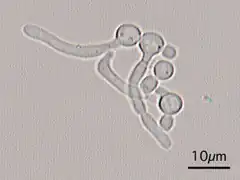

C. albicans exhibits a wide range of morphological phenotypes due to phenotypic switching and bud to hypha transition. The yeast-to-hyphae transition (filamentation) is a rapid process and induced by environmental factors. Phenotypic switching is spontaneous, happens at lower rates and in certain strains up to seven different phenotypes are known. The best studied switching mechanism is the white to opaque switching (an epigenetic process). Other systems have been described as well. Two systems (the high-frequency switching system and white to opaque switching) were discover by David R. Soll and colleagues.[41][42] Switching in C. albicans is often, but not always, influenced by environmental conditions such as the level of CO2, anaerobic conditions, medium used and temperature.[43] In its yeast form C. albicans ranges from 10 to 12 microns.[44] Spores can form on the pseudohyphae called chlamydospores which survive when put in unfavorable conditions such as dry or hot seasons.[45]

Although often referred to as dimorphic, C. albicans is, in fact, polyphenic (often also referred to as pleomorphic).[46] When cultured in standard yeast laboratory medium, C. albicans grows as ovoid "yeast" cells. However, mild environmental changes in temperature, CO2, nutrients and pH can result in a morphological shift to filamentous growth.[47][48] Filamentous cells share many similarities with yeast cells. Both cell types seem to play a specific, distinctive role in the survival and pathogenicity of C. albicans. Yeast cells seem to be better suited for the dissemination in the bloodstream while hyphal cells have been proposed as a virulence factor. Hyphal cells are invasive and speculated to be important for tissue penetration, colonization of organs and surviving plus escaping macrophages.[49][50][51] The transition from yeast to hyphal cells is termed to be one of the key factors in the virulence of C. albicans; however, it is not deemed necessary.[52] When C. albicans cells are grown in a medium that mimics the physiological environment of a human host, they grow as filamentous cells (both true hyphae and pseudohyphae). C. albicans can also form chlamydospores, the function of which remains unknown, but it is speculated they play a role in surviving harsh environments as they are most often formed under unfavorable conditions.[53]

Diagnosis